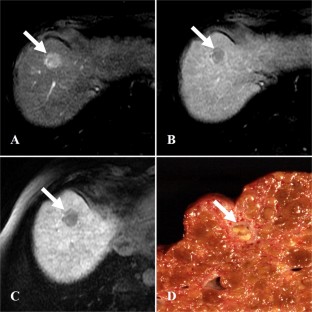

Fig. 2